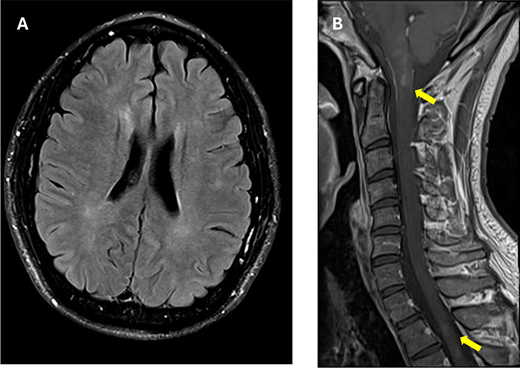

The patient’s magnetic resonance imaging (MRI) at 10 months after the seizure onset. He had intermittent paresthesia in the left leg, and his reflexes were increased in his right arm and leg. A, Axial fluid-attenuated inversion recovery (FLAIR) imaging of the brain shows ill-defined hyperintense lesions in the periventricular regions. B, Sagittal T1-weighted image of the spinal cord shows new short hyperintense lesions affecting the brainstem, the cervical spinal cord, and upper thoracic spinal cord (arrows).